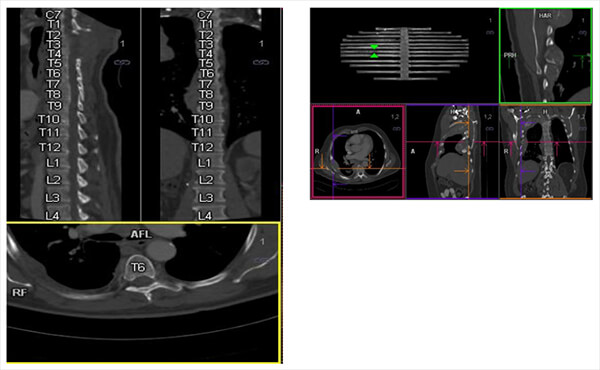

Multiplanar

The curved multiplanar axis allows the draw of a central axis inside a structure independently from its origin. (vascular or other).Visualization of sagittal and coronal vertebrae in the same plan. Also a Visualization of the coast in the same plan.